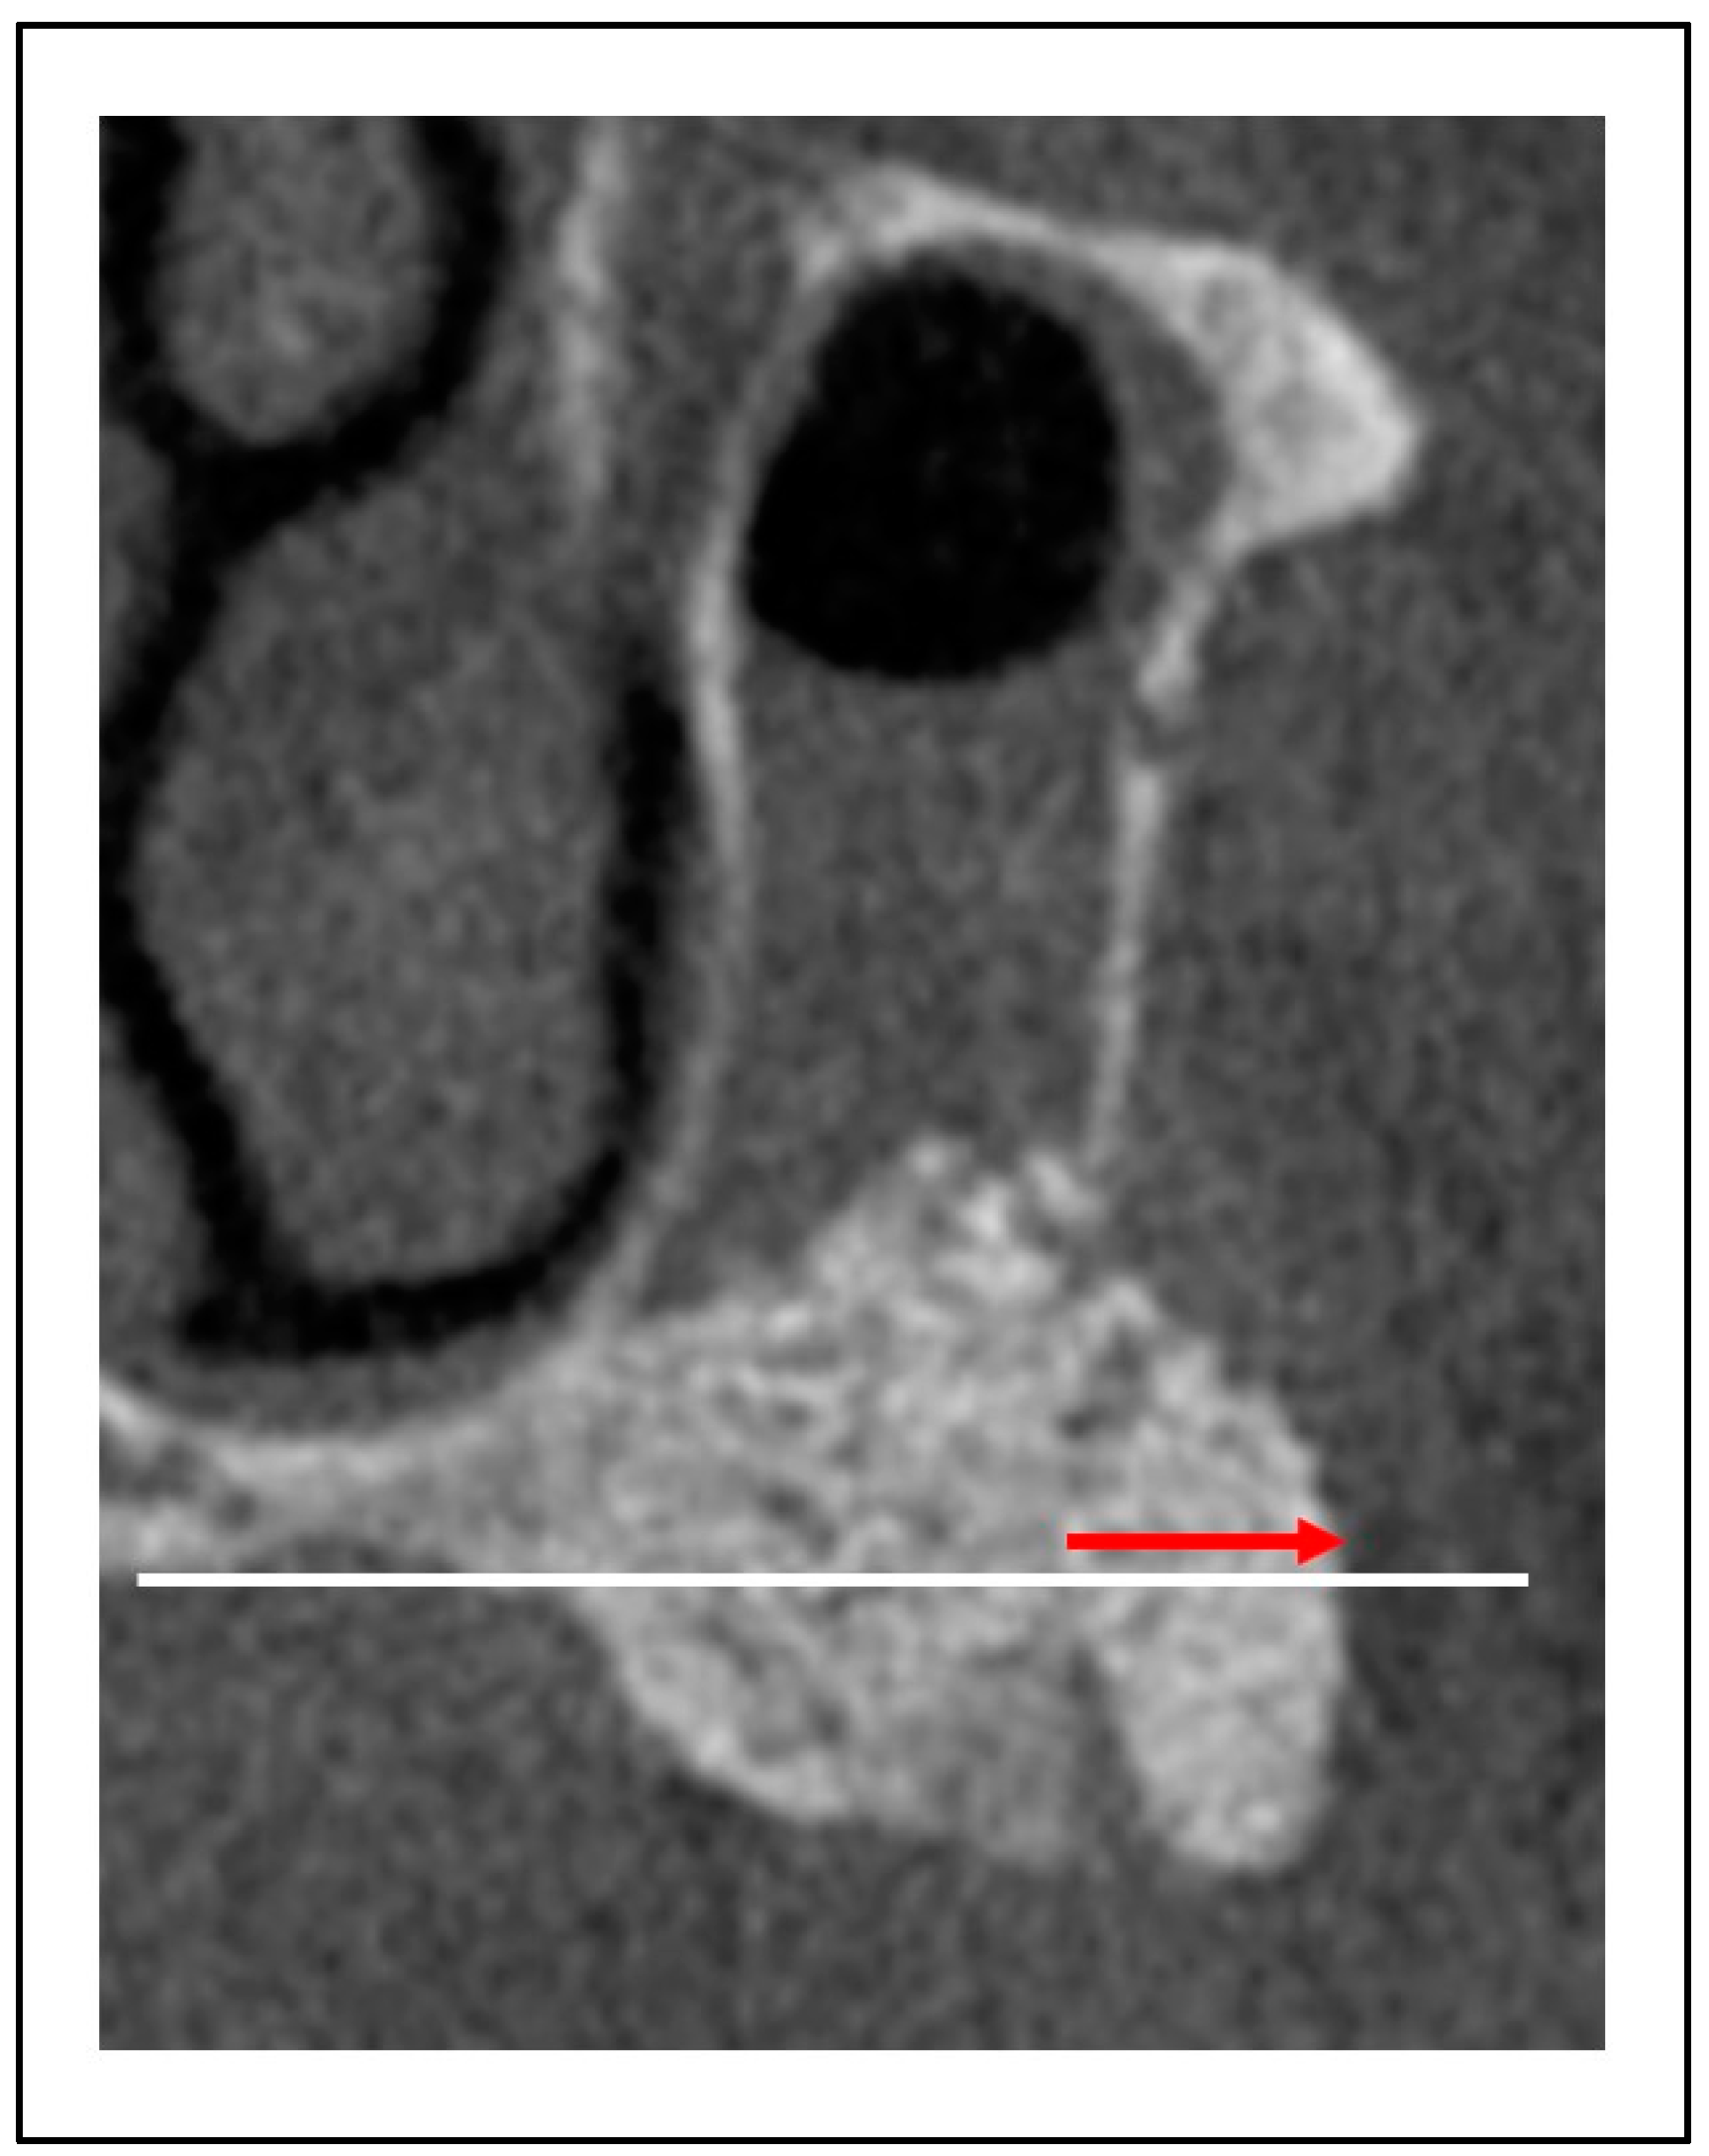

- Ohayon, L.; Taschieri, S.; Friedmann, A.; Del Fabbro, M. Bone Graft Displacement After Maxillary Sinus Floor Augmentation With or Without Covering Barrier Membrane: A Retrospective Computed Tomographic Image Evaluation. Int. J. Oral Maxillofac. Implants 2019, 34, 681–691. [Google Scholar] [CrossRef]

- Nagata, K.; Fuchigami, K.; Kitami, R.; Okuhama, Y.; Wakamori, K.; Sumitomo, H.; Kim, H.; Okubo, M.; Kawana, H. Comparison of the Performances of Low-Crystalline Carbonate Apatite and Bio-Oss in Sinus Augmentation Using Three-Dimensional Image Analysis. Int. J. Implant Dent. 2021, 7, 24. [Google Scholar] [CrossRef] [PubMed]